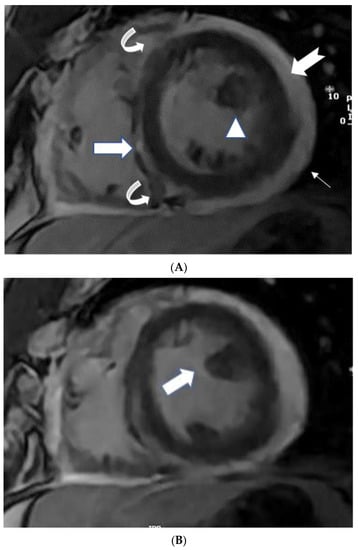

Figure 1.

(A) A 35-year-old male with a recent history of treated tuberculous pericarditis for six months had CMR for ventricular tachycardia. 2CH T2w STIR pictures demonstrate increased epicardial and transmural signals in the inferior wall (arrows). (B) A 35-year-old male with a recent history of treated tuberculous pericarditis for six months had CMR for ventricular tachycardia. 4CH T2w STIR pictures demonstrate irregular thickening of the pericardium (small arrows) with the increased transmural signal of the mid-lateral wall (thick arrow).

Figure 2.

(A) A 35-year-old male with a recent history of treated tuberculous pericarditis for six months had CMR for ventricular tachycardia. Short axis mid myocardial slice, late enhancement images, shows subepicardial anterolateral (notched arrow), mesocardial mid and inferior septal (white arrow), anterior and posterior RV insertion points (curve arrow) with thickened pericardium and epicardial fat enhancement (thin arrows). Enlarged AL papillary muscle (arrowhead). (B) A 35-year-old male with a recent history of treated tuberculous pericarditis for six months had CMR for ventricular tachycardia. Short axis mid myocardial slice late enhancement images show all the features of (A) and asymmetrical enlargement of the AL papillary muscle (arrow). (C) A 35-year-old male with a recent history of treated tuberculous pericarditis for six months had CMR for ventricular tachycardia. Short axis mid myocardial slice late enhancement images show the RV lateral and inferior wall (arrow), superior and inferior insertion (white arrow) with epicardial fat enhancement (thin arrows). PM papillary muscle is with central enhancement (arrowhead).

The thickness of the pericardium has long been recognized as a strong predictor of constrictive pericarditis [40,41]. The thickness of the pericardium varied between 1.5 and 3.9 mm in several locations with tuberculous myopericarditis (Figure 1B). On pathologic examination, the maximum pericardial thickness varies significantly (1–17 mm; mean, 4 mm) in patients with pericardial constriction (96%), with up to 20% of patients having a regular (2-mm) thickness [40,41]. According to Feng et al., the pericardial thickness was significantly lower in individuals with chronic constrictive pericarditis than in those with reversible constrictive pericarditis (2 mm ± 1 vs. 4 mm ± 1; p > 0.001) [42]. Thus, patients with end-stage constrictive pericarditis had a narrower pericardium than those with chronic inflammation that survived. In addition, CMR tagging techniques may be advantageous for precisely displaying fibrotic pericardial adhesions [32].